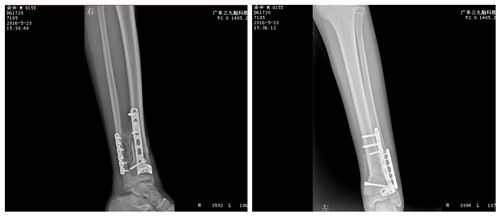

▲术后DR

2016年4月15日,在全麻下为患者进行左胫腓骨远端骨折切开复位内固定术,术中出血约100ml,手术历时约2小时。术后患者经过抗炎消肿等治疗,顺利度过肿胀期、感染期。

【专家点评】患者左胫腓骨远端骨折粉碎严重,临近骨骺,考虑骨折固定要牢固,并且不能损伤骨骺,手术难度巨大。术前有建议克氏针固定以及手法复位等方法。首先克氏针固定不牢固,其次克氏针固定、手法复位等均需要长时间外固定,不利于这样重症病人的护理,极易产生压疮以及坠积性肺炎;坚强内固定利于患者早期功能锻炼,避免外固定利于患者体位护理。

患者粉碎性骨折内固定首选锁定钢板。钢板固定的难度在于骨折远端内侧骨块尺寸不大,考虑稳定固定起见,必须固定2-3颗螺钉。所以术前打印3D模型,根据模型选择复位方案以及内固定选择、塑形,大大缩短内固定时间,减少患肢肿胀,利于患者恢复。